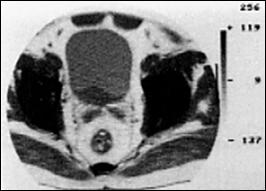

4.3. Tomografia computerizata si rezonanta magnetica nucleara

Informatiile furnizate de aceste metode moderne imagistice ridica procentajul acuratetei diagnostice pana la 85% in aprecierea infiltratiei parietovezicale a tumorilor (T) si la circa 90% pentru decelarea adenopatiei pelviene.

Figura 37. Aspect

tomografic de tumora vezicala. Formatiune tumorala

exofitica protruziva intravezical situata pe peretele

postero-lateral stang. Figura 38. CT pelvin - Tumora voluminoasa in hemivezica

dreapta Figura 39. CT abdominal - Adenopatie extraregionala

periaortico-cava